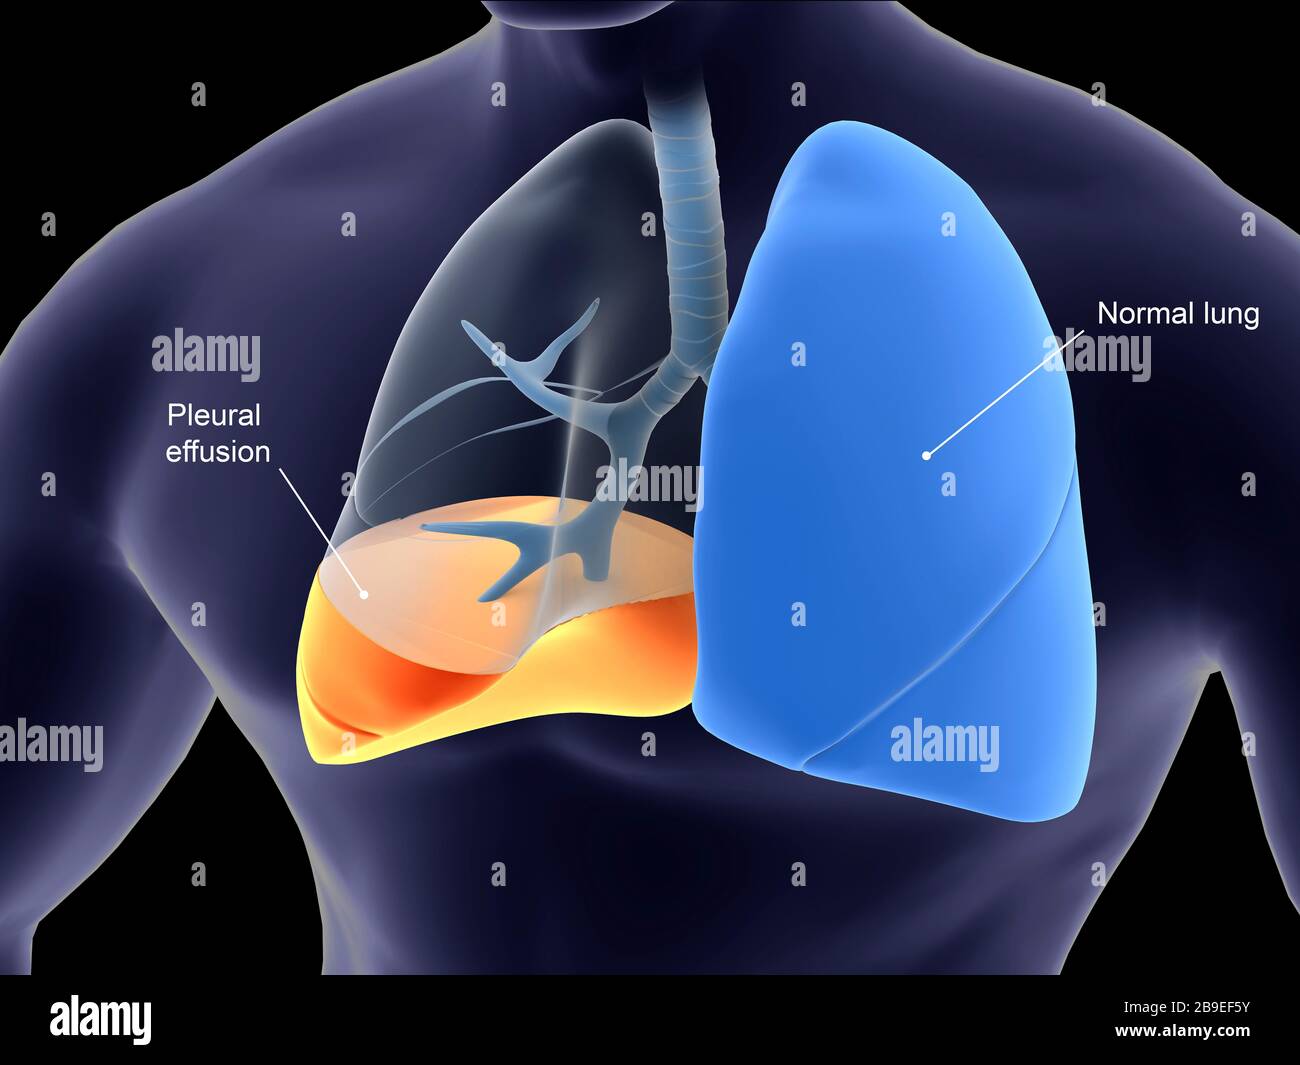

Симптомы и причины скопления воды в легких